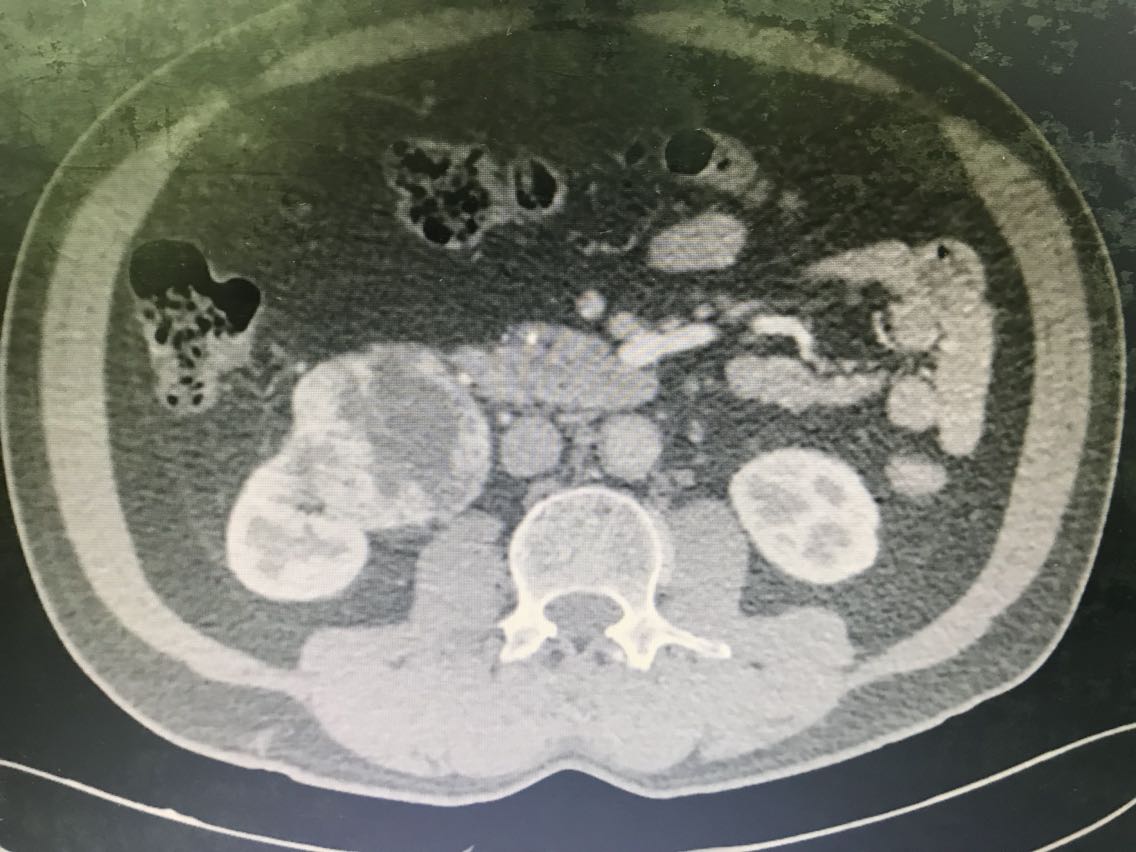

患者男性,62岁。 主诉:咯血、体检发现右肾占位1+月 现病史:1+月前,患者无明显诱因出现反复咯血,为痰中带鲜血,无胃内容物,无畏寒、发热,无胸闷、胸痛,无潮热盗汗,无恶心、呕吐,无腹胀、腹痛等不适。于当地医院就诊,行相关检查(具体报告未见)考虑“支气管扩张”,行相关治疗(具体不详)后患者咯血症状好转出院。患者于住院期间检查发现右肾占位(报告未见),无腰痛、腰胀,无血尿、蛋白尿,无尿少及排尿困难。患者为进一步诊治,于我院门诊就诊,查肝肾功能、肿瘤标志物、小便常规未见明显异常。上腹部增强CT:右肾前下份占位,考虑透明细胞癌(T3aN2Mx),左肾结石、囊肿,腹膜后多发淋巴结,肝脏右后叶下段小囊肿,腹主动脉管壁钙化。现患者为进一步明确诊断及治疗,入住我科。 既往史无特殊。

查体无特殊。 辅助检查: 心电图:窦性心律,电轴左偏,左前分支阻滞,不完全性右束支阻滞。 上腹部增强CT:右肾前下份占位,考虑透明细胞癌(T3aN2Mx),左肾结石、囊肿,腹膜后多发淋巴结,肝脏右后叶下段小囊肿,腹主动脉管壁钙化。